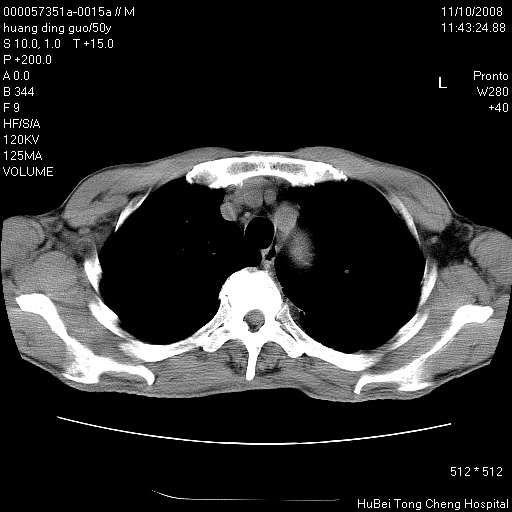

患者 男,50岁。左侧腰背部疼痛3月余,伴消瘦。平素健康,无传染病史。

胸部ct轴位平扫(层厚10mm,螺距1.5,重建间隔10mm),图像如下:

左肺下叶背段有一厚壁空洞,外壁呈锯齿状伴毛刺改变。空洞相邻胸膜有牵拉改变。左肺下叶血管支气管束不规则增粗,小叶间隔增厚。胸椎骨质破坏。考虑左肺下叶周围型肺癌伴左肺下叶癌性淋巴管炎、胸椎转移。

支持:左肺周围型肺癌伴癌性淋巴管炎\\胸椎转移瘤,不除外肺泡癌。(椎体破坏伴椎弓破坏)

左肺下叶背段有一厚壁空洞,内壁不规则,外壁呈锯齿状伴毛刺改变。空洞相邻胸膜有牵拉改变。周围呈絮状炎性改变,左肺下叶血管支气管束不规则增粗,小叶间隔增厚。胸椎骨质破坏。考虑左肺下叶周围型肺癌伴左肺下叶阻塞性肺炎、胸椎转移。